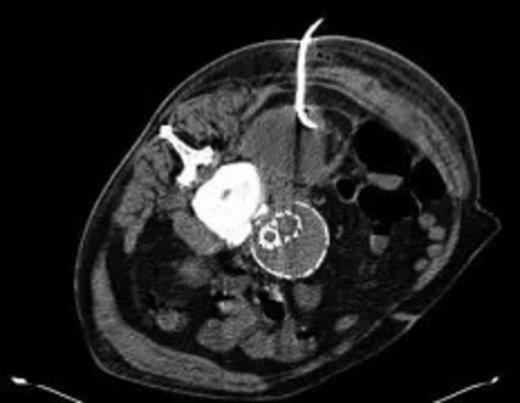

Four weeks following discharge the patient was re-admitted with feeling increasingly unwell, recurrent pyrexia, loss of appetite and mild shortness of breath on exertion. Physical examination was unremarkable except for a temperature of 38.3 centigrade. Blood tests on admission showed Hb 11.4 g/dl (11.5-16.0 g/dl), white cell count 13.1×109/L (4-9.2 x 109/L) and CRP 68mg/L (<3 mg/L). Contrast enhanced CT scan (Fig. 2,3) showed a 50 mm maximum retroperitoneal collection situated between the right kidney and the right iliac vessels. It contained a few loculi of gas. A diagnosis of postoperative right psoas abscess was made. The patient was started on intravenous broad spectrum antibiotics – Tazocin (Piperacillin+ Tazobactam) and Metronidazole. CT guided drainage was carried out using a 10 French gauge pigtail catheter locked pigtail (Meditech Flexima regular all-purpose drainage catheter sets with locking pigtail (Boston Scientific)) (Fig. 4). The isolation of E. coli from the collection with negative Hemocultures suggested a bowel source for the infection but no actual breach was demonstrable. The bowel surgeons ruled out colonic pathology.

CT guided drainage was carried out using a 10 French gauge pigtail catheter locked pigtail (Meditech Flexima regular all-purpose drainage catheter sets with locking pigtail (Boston Scientific))